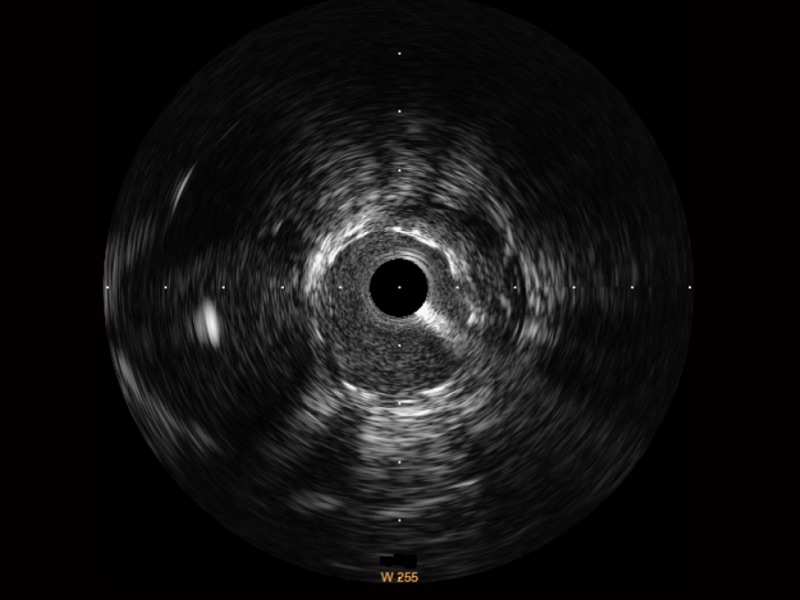

美狮贵宾会官网超宽频成像技术覆盖20-80MHz1或20-90MHz2频率范围, 提供优异的分辨力同时也保证充足的穿透深度

对比传统IVUS导管成像,美狮贵宾会官网宽频IVUS图像的近场支架梁显影更细腻,远场中膜外血管仍清晰可辨,兼顾远中近,兼顾分辨力与穿透深度